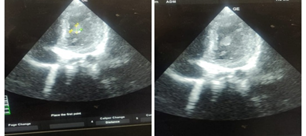

Laboratory parameters are summarized in Table 1. Complete blood count revealed neutrophilic leukocytosis with lymphopenia. Prothrombin time was 19 sec, activated partial thromboplastin time was 35.63 sec and International Normalised Ratio was 1.5. Initial ECHO showed mild LV dysfunction with ejection fraction of 41% and minimal pericardial effusion. Right coronary artery showed an aneurysm with a Z score of +2.54 and other coronaries were normal. Her inflammatory markers were elevated with D-dimer of 6.65 μg/ml (Reference range < 0.46 µg/ml) and IgG covid antibody was positive with a titre of 83.77 AU/ml (Reference range < 10 AU/ml). She was covid RT PCR negative. With a possible diagnosis of MIS-C she was started on intravenous immunoglobulin at 2 g/kg and methylprednisolone at 10 mg/kg/day. Serial echo revealed fall in EF with lowest value of 33% [Table 2] and thrombi at the left ventricular apex and interventricular septum as shown in Figure 1. In view of right fundal bleeds aspirin and heparin were withheld. Neuroimaging revealed infarct over the left frontoparietal region [Figure 2]. Child had persistent fever spikes and fall in hemoglobin and platelet counts. Bone marrow aspiration showed hemophagocytic lymphohistiocytosis. Fever work up including blood culture, urine culture, enteric fever, dengue, leptospirosis and scrub serology were negative.

Figure 1. ECHO showing Left ventricle thrombus along Interventricular septum.